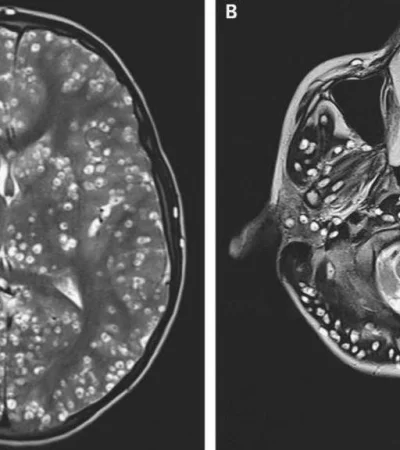

El joven, de quien se preserva su identidad, fue sometido a una resonancia magnética donde se descubrió la gran cantidad de huevos de parásitos en la corteza cerebral, en el tronco cerebral (incluido el cerebelo) y por encima de la médula espinal.

El diagnóstico fue determinante: neurocisticercosis. Se trata de una enfermedad de origen parasitario que es causada cuando un individuo ingiere huevos de Tenia. Las larvas se arrastran fuera de los huevos hacia los tejidos musculares y cerebrales, donde forman quistes, informó CNN en español. Además los médicos descubrieron quistes en el ojo derecho y el testículo derecho del paciente.